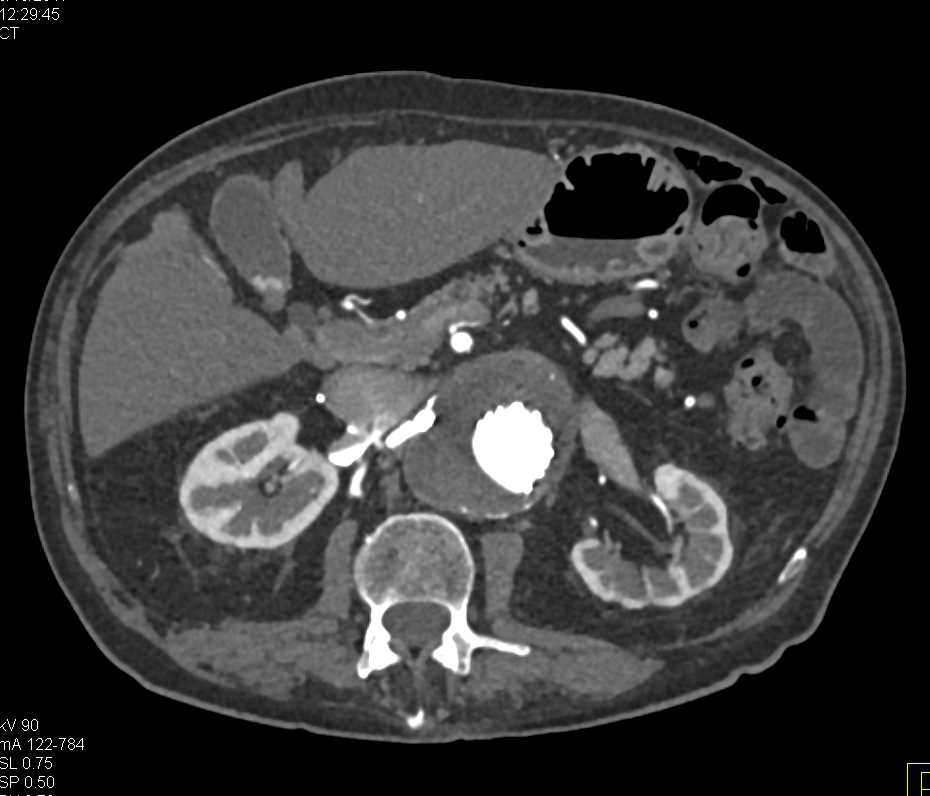

Diagnosis

Bleed Left Thigh with Graft